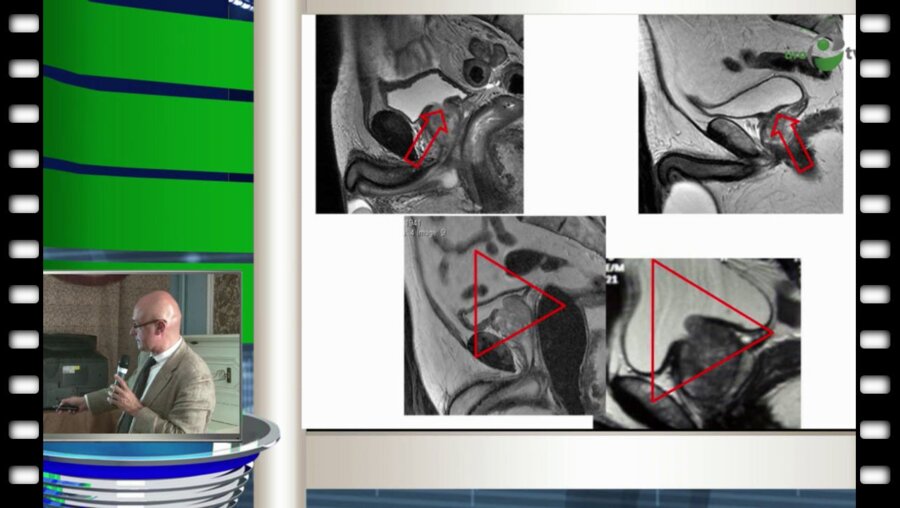

1113-е заседание Московского общества урологов

27 мая 2014